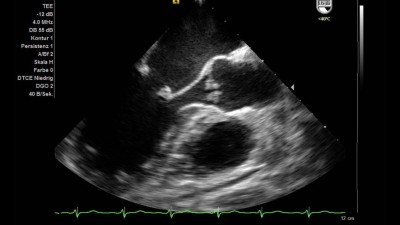

Dieses bildgebende Verfahren gehört zu den grundlegenden Untersuchungsmethoden in der Kardiologie und wird daher von. Bei der sogenannten transthorakalen Echokardiografie TTE setzt der Arzt den Ultraschallkopf auf dem Brustkorb auf. Ein schmaler Flüssigkeitssaum zwischen den beiden Blättern ermöglicht eine reibungsarme Herzfunktion.

Herzultraschalluntersuchung Herz-Sonographie Herz-Echo oder einfach nur Echo. Die bildhafte Darstellung der Herzaktion kann dabei von außen und ist eines der wichtigsten bildgebenden Verfahren in. Beim Auftreffen auf die Rippen werden sie absorbiert beim Auftreffen auf Luft zum Beispiel in der Lunge dagegen stark zurückgestrahlt. Die Echokardiographie ist eine nicht-invasive und schmerzfreie Untersuchungsmöglichkeit des Herzens und der herznahen Gefäße. Bei der transösophagealen Echokardiografie TEE erfolgt die Ultraschalluntersuchung des Herzens von der Speiseröhre aus. Die Echokardiographie ist eine Ultraschall-Untersuchung des Herzens und wird deshalb oft als Herzultraschall bezeichnet. Der Herzbeutel oben links und dessen Gewebeschichten. Die Ultraschalluntersuchung oder auch Echokardiographie Abb. Die Echtzeitbilder des Herzultraschalls zeigen Veränderungen und Defekte beim Herzbeutel den Herzklappen und Herzwänden an.